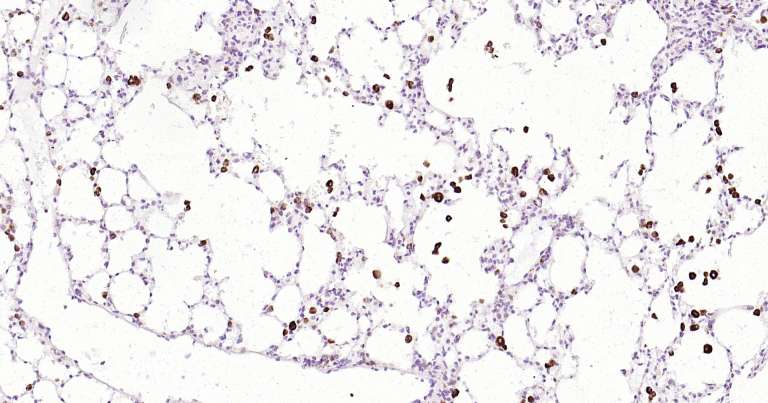

產品圖片

Immunohistochemical analysis of paraffin embedded mouse liver tissue slide using IHC0302M (Mouse CD68 IHC Kit).

Immunohistochemical analysis of paraffin embedded mouse lung tissue slide using IHC0302M (Mouse CD68 IHC Kit).